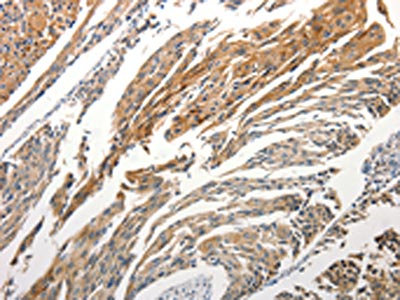

The image is immunohistochemistry of paraffin-embedded Human cervical cancer tissue using CSB-PA105672(STAT5B Antibody) at dilution 1/25. (Original magnification: ×200)